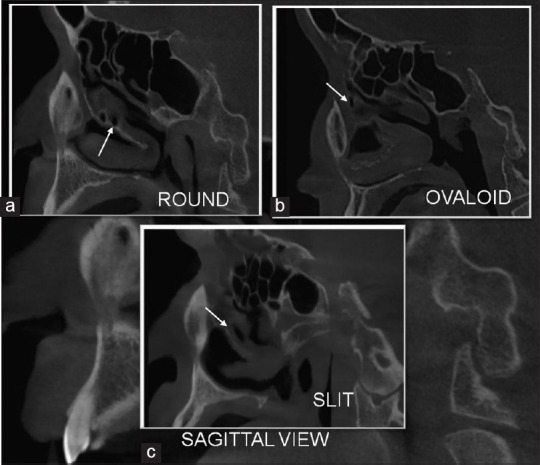

Results: Between the male and female groups, differences on both the right and left sides with respect to the MS height were observed (P > 0.05). However, the male group showed statistically significant higher values for right-sided MS width (P < 0.05). The prevalence of AMO in 400 MSs was found to be 65%, of which 63% of AMOs were present in the male group. The prevalence of types of accessory maxillary ostia revealed that the round and ovoid shapes were similar in number as compared to slit shapes.